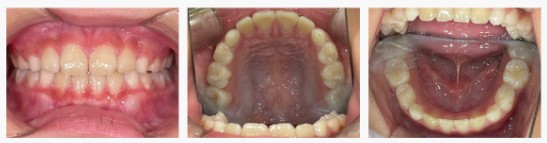

▼After(治療後)

治療を進めるうちに、舌の位置と呼吸の仕方が安定し、あごの幅が自然に広がってきました。

その結果、前歯の重なりが軽減し、歯列がきれいなアーチ状に整いました。

お子さまご自身も「歯がきれいに並んできた!」と嬉しそうに鏡を見てくれるようになり、笑顔も増えました。

また、姿勢や口呼吸の改善も見られ、全身の成長にも良い影響が確認できました。